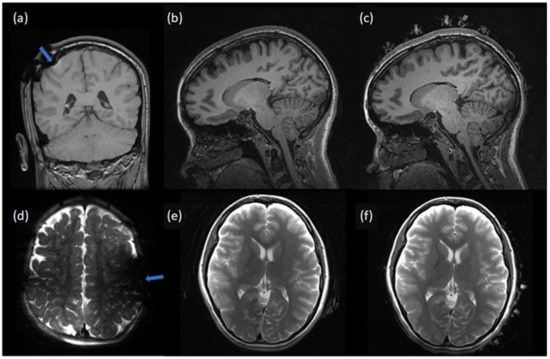

| Scan | NeoNet EEG | Reviewer 1 | Reviewer 2 | |

|---|---|---|---|---|

| Subject 1 | T1 | No | 4 | 4.5 |

| T1 | Yes | 4 | 4.5 | |

| Subject 2 | T1 | No | 5 | 5 |

| DTI | No | 4 | 5 | |

| T1 | Yes | 5 | 5 | |

| DTI | Yes | 4 | 5 | |

| Subject 3 | T1 | No | 5 | 5 |

| T2 | No | 4 | 4.5 | |

| T2 | Yes | 4 | 4 |